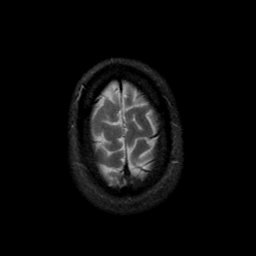

MR Study #9, April 14, 1991 -- Slice #45

[Home][Help][Clinical][Tour 1][Tour 2] Slice 45